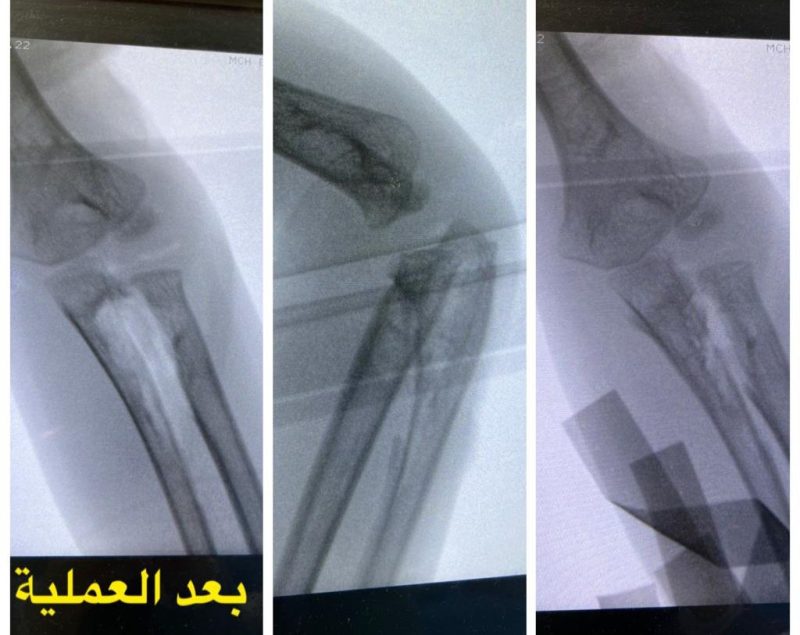

نجح فريق طبي متخصص بجراحة المفاصل والعظام في مستشفى الولادة والأطفال ببريدة بإنهاء معاناة طفل يبلغ من العمر أربعة أعوام كان يشكو من عدم المقدرة على تحريك عظام الساعد الأيسر منذ ولادته.

وأوضح تجمع القصيم الصحي أن عيادة جراحة العظام للأطفال في المستشفى استقبلت الطفل برفقة ذويه، وبعد القيام بعمل المعاينة السريرية وإجراء الفحوصات والأشعة المقطعية اللازمة تبين أن الطفل مصاب بالتحام خلقي في عظام الساعد الأيسر، مما جعله يفقد الحركة الدورانية المعتادة للساعد بشكل تام.

جراحة دقيقة

وبين أن المستشفى أجرى العمل الجراحي اللازم للطفل وذلك باستئصال الجزء الزائد غير الطبيعي الذي يصل بين العظمين، كما تم وضع مادة وأنسجة فاصلة بين العظمين لتجنب حدوث الالتحام، وقد تم التأكد سريرياً من عودة الحركة للساعد بشكل كامل عقب الانتهاء من العمل الجراحي، بالإضافة إلى إجراء التصوير الشعاعي أثناء تنفيذ العملية بنجاح، ليغادر الطفل بعدها المستشفى برفقة ذويه مصحوباً بالعافية.